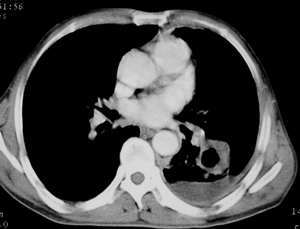

以下是引用sdqzwyx在2005-11-7 19:59:00的发言:[br]双肺弥漫大小不等的粟粒状结节影;肺纹理走行失去自然,粗细不均,边缘不规则,小叶间隔增厚;左上肺示不规则形致密影,从斑块边缘向周围伸出长短不一的致密索条影,临近的血管、支气管和叶间胸膜等结构受牵拉移位;左下肺示不规则团块状影,其内示空洞,洞内壁尚光整,左侧胸腔积液。右肺下叶背段亦示部分病灶融合。双肺可见局限性肺气肿。[br]诊断:结合病史符合三期矽肺表现(少数矽肺纤维斑块内可以形成空洞,一般认为是斑块中央感染引起坏死所致)但尘肺病人易合并肺结核,诊断可为三期+tb。所以此病人应进一步检查是否合并结核。